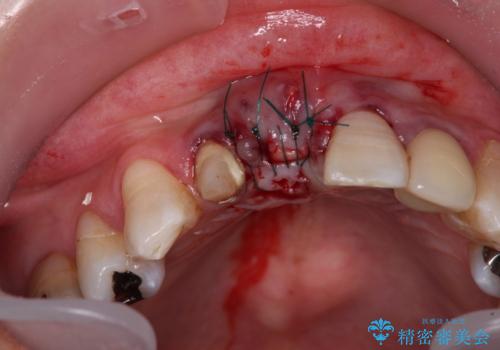

事前に仮歯を用意し、中切歯を抜歯した後に側切歯を土台とした仮歯を装着することで、審美的な問題が起こらないようにすることとしました。

側切歯は根管治療を行い、中切歯部は骨の再生を待ってインプラントを埋入し、その後2本合わせてオールセラミッククラウンにて補綴治療を行うこととしました。

現在では、抜歯時にインプラントを埋入し。同時に仮歯を装着する「抜歯即時埋入・即時荷重インプラント」での取り扱いとなりますが、治療当時は未導入であったため、従来の複数回の外科処置を行う術式で治療を行いました。そのため、歯肉の位置が上方に移動した位置での仕上がりとなりました。